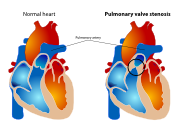

| 18:30, 9 October 2012 | Pulmonary valve stenosis.svg (file) |  |

59 KB | Description: The diagram shows a healthy heart and one suffering from Pulmonary valve stenosis. Date: 12 June 2006 Author: Mariana Ruiz LadyofHats | 1 |